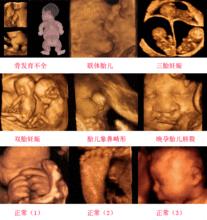

B超查寶寶的五官 、四肢以及內部各個器官有無異常,驗血驗尿屬於一般性的常規檢查,主要是看是否貧血。建議16---20周唐氏篩查,空腹抽血--主要篩查胎兒神經管畸形,

24周左右做三維彩超,可清晰顯示胎兒各部位臟器,了解胎兒生長發育情況,觀察頭,肢體及各臟器大體結構是否有畸形.。另外還要定期檢查胎心、血壓等等。具體可向當地醫院或婦幼保健站詳詢!